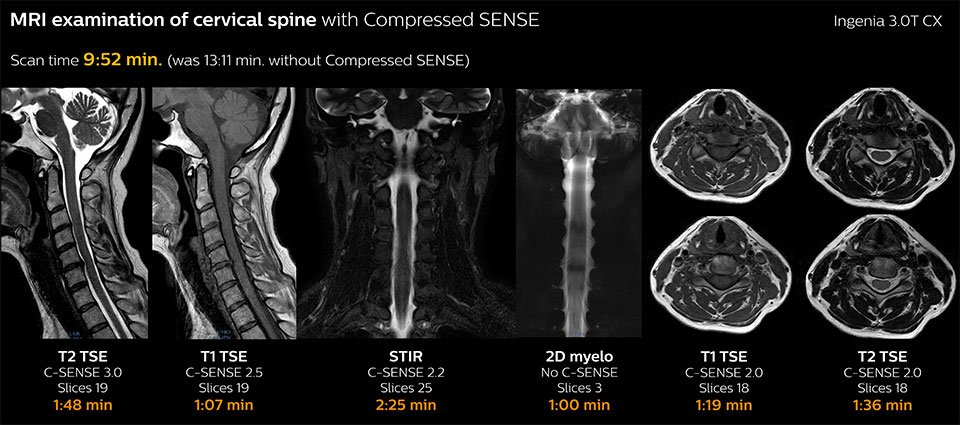

Fast MRI of cervical spine

With Compressed SENSE, the scan time for the routine cervical spine examination at KNC was reduced from 13:11 to 9:52 minutes, which corresponds to 25% reduction.

MRI examination of the cervical spine with Compressed SENSE

Ingenia 3.0T CX

Scan time 9:52 min. (was 13:11 min. without Compressed SENSE)